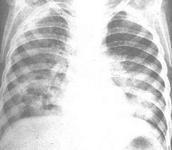

老年人終末期肺炎癥狀

• 老年人終末期肺炎

628健康網為您分享有關老年人終末期肺炎的癥狀,老年人終末期肺炎的治療方法,老年人終末期肺炎的預防知識,老年人終末期肺...